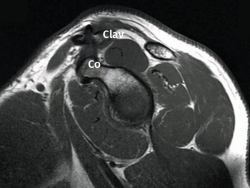

Figura 1. Caso demostrativo de la luxación con la sujeción por parte del paciente de 2 kg de peso.

La exploración clínica se realizó mediante la valoración del denominado signo de la “tecla” (desplazamiento vertical) y del desplazamiento horizontal. Se completó el diagnóstico mediante radiografía simple anteroposterior (AP) comparativa de ambos hombros. En los casos de duda en relación con el grado de la lesión, esta proyección se realizó con la sujeción por parte del paciente de 2 kg de peso (Figura 1). No se creyó necesaria la realización sistemática de tomografía axial computarizada (TAC) ya que la exploración y la exploración bajo anestesia permiten establecer las direcciones y la importancia del desplazamiento. Tampoco se realizó resonancia, dado que la artroscopia permitiría, como así se demostró, diagnosticar posibles lesiones asociadas.